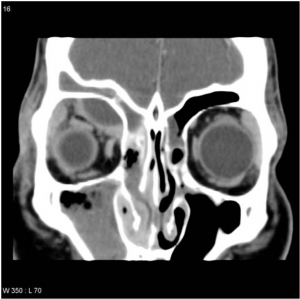

Dacrocystography (DCG)

For anatomic evaluation of the lacrimal system. It tells us about the exact level of obstruction or stenosis and the presence of diverticulum, fistula, stones, or tumours. CT-DCG show adjacent bony structures also. During the procedure, dye is injected into bilateral lacrimal systems and magnified images then are obtained.[46] There are two types :

Macro DCG

X-Ray based. An erect scan delayed by 5 minutes post injection of contrast is taken.

Micro DCG

Computed tomography (CT-DCG)/magnetic resonance imaging (MRI-DCG) scan based.